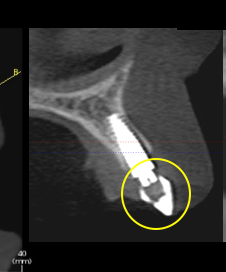

Many different types of guides may be fabricated and utilized. In today’s implant world, many guides are three-dimensional, CAD/CAM guides designed from cone beam radiologic imaging. These guides are fabricated with specific guide holes that direct the position and depth of the implant drill for a very calculated implant placement.

Although these guides are very precise, to within hundredths of millimeters, there are some limitations. These guides do not allow for intra-surgical visualization of the apical gingival contour of the proposed restoration.

In reality, these guides create a “blind” placement of implants. Fabrication of a simple surgical guide that allows for intra-operative visualization of the proposed tooth outline and implant angulation can be a practical addition to a successful outcome. It also provides effective communication between the implant surgeon and the restorative dentist.

The surgeon can easily alternate between the cone beam scan guide and the “analog” tooth visualization guide. Each guide provides the necessary information to place implants for restoration predictability and longevity ideally. Cone beam scan guides are “state of the art” for surgeons in today’s world for the accuracy of implant placement. “Simple” surgical guides, fabricated from the diagnostic wax-up and the expertise of the restorative dentist, provide the precision and detail required for a successful “crown down” implant restoration.

Through these software programs, implant placement is directed and planned based on the detailed information provided by the cone beam X-ray. The implants may be “digitally” placed with high accuracy. Surgeons are very reliant on these software tools.